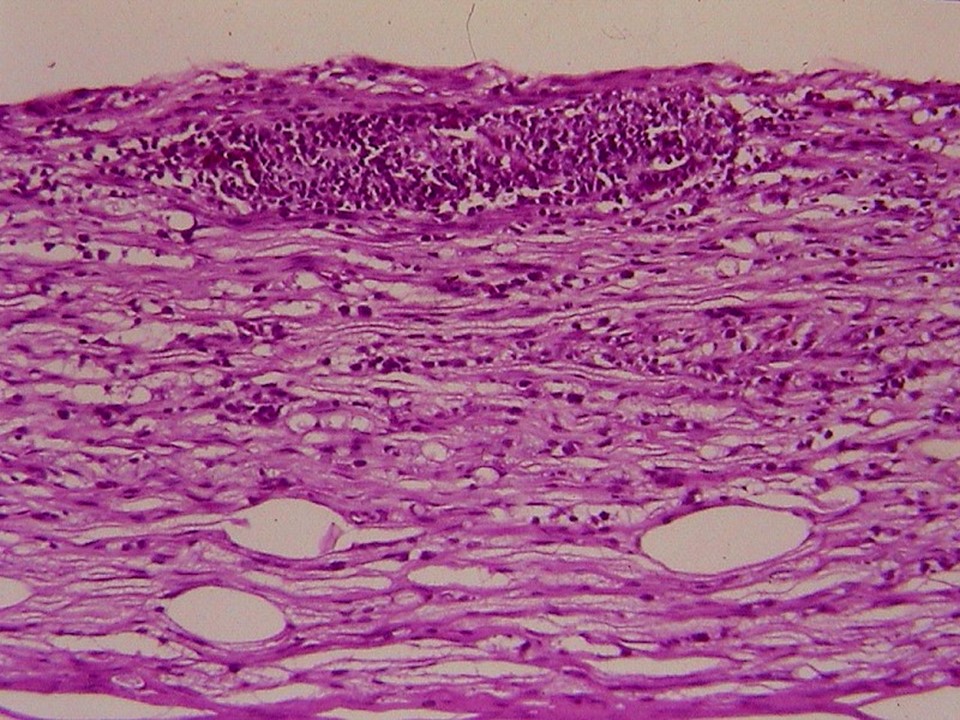

疾病中文名稱:馬立克病

疾病英文名稱:Marek's disease

影像說明:翼神經受侵犯而翅膀下垂,坐骨神經受侵犯呈劈腿狀